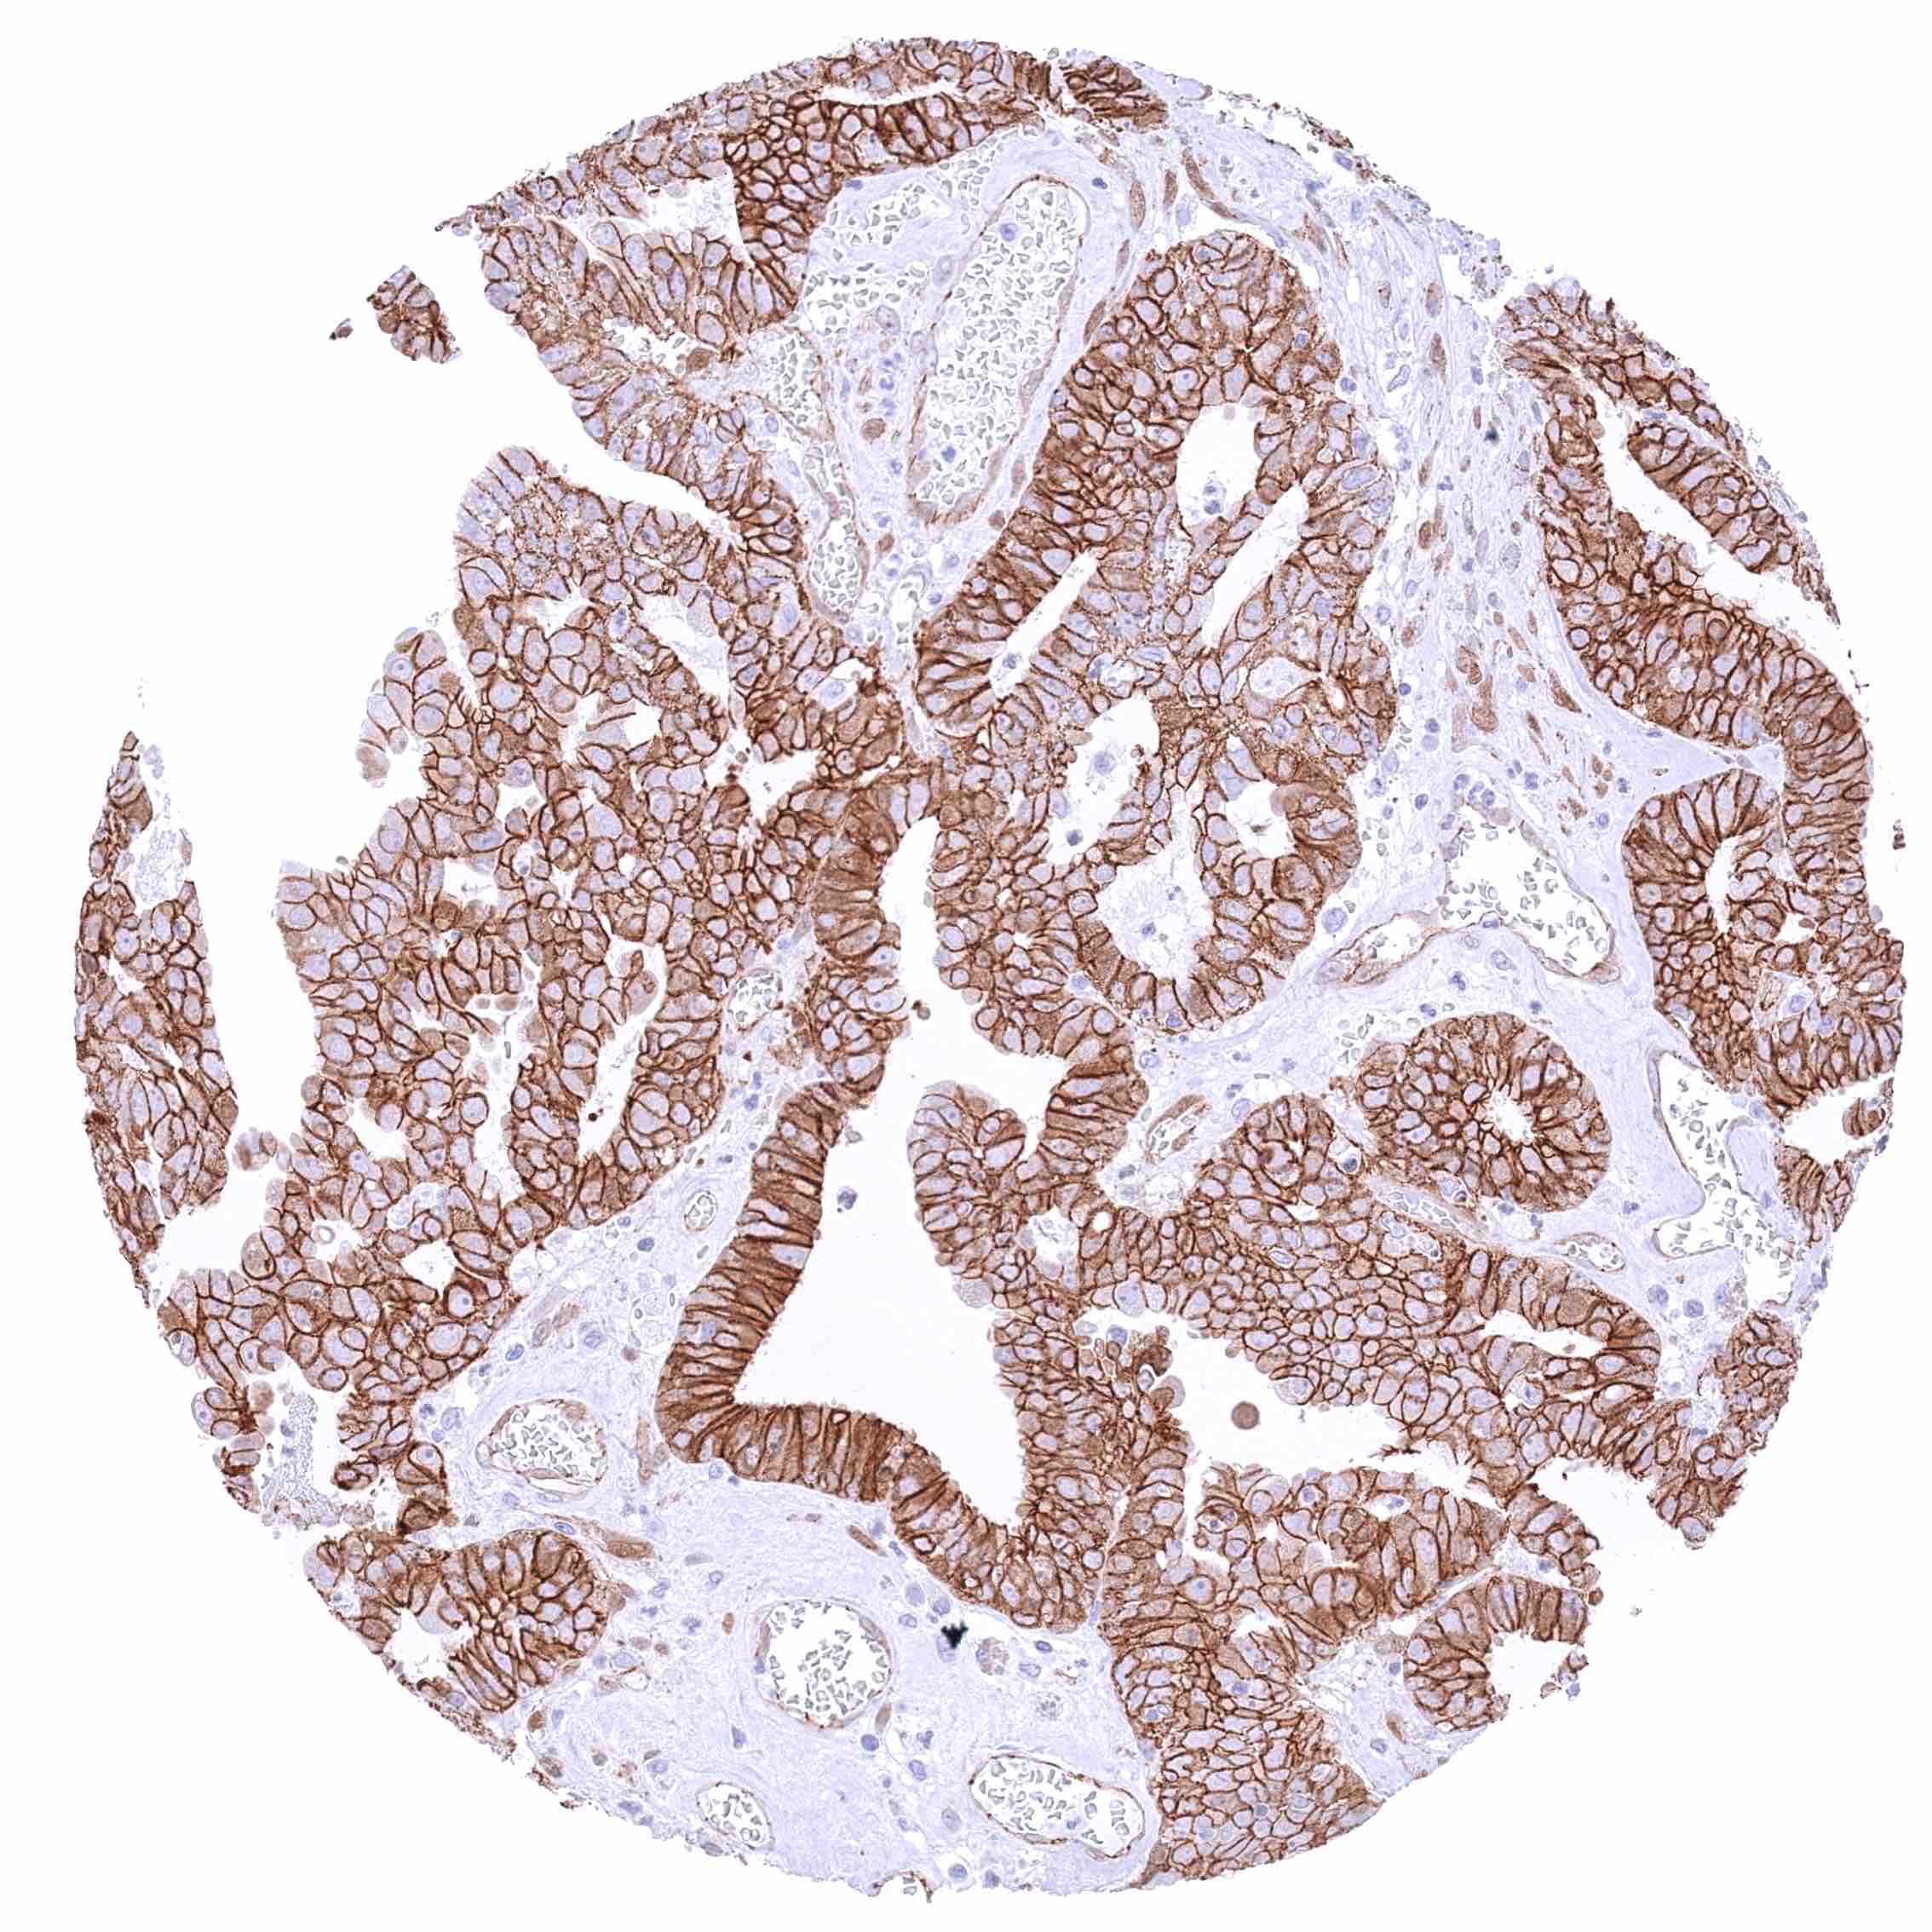

Pancreas – Ductal adenocarcinoma with strong membranous β-Catenin staining of tumor cells possibly accompanied by a mild cytoplasmic positivity.